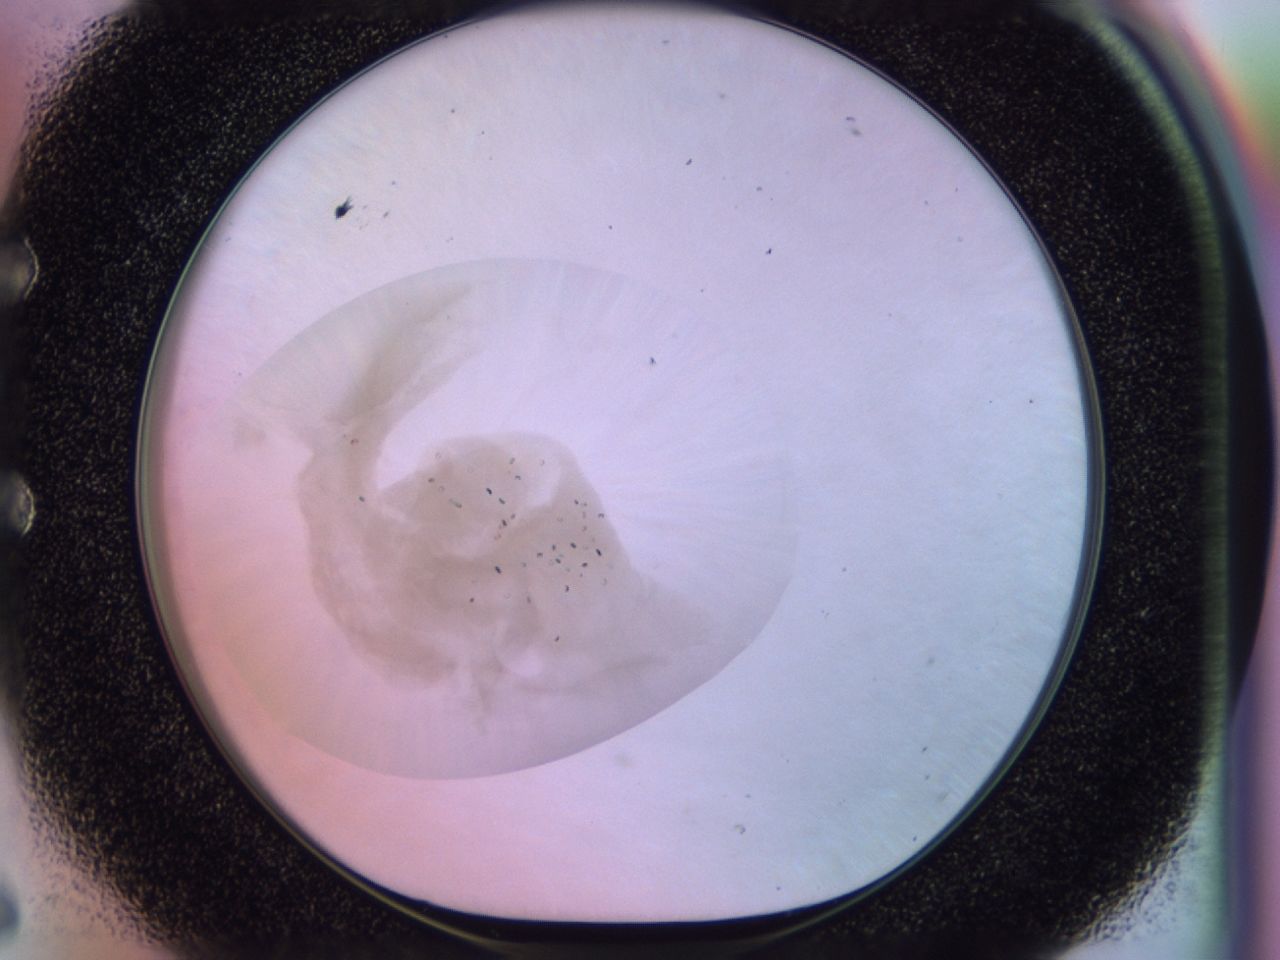

Image 2090

Precipitate

00ph_E6_ImagerDefaults_3.jpg